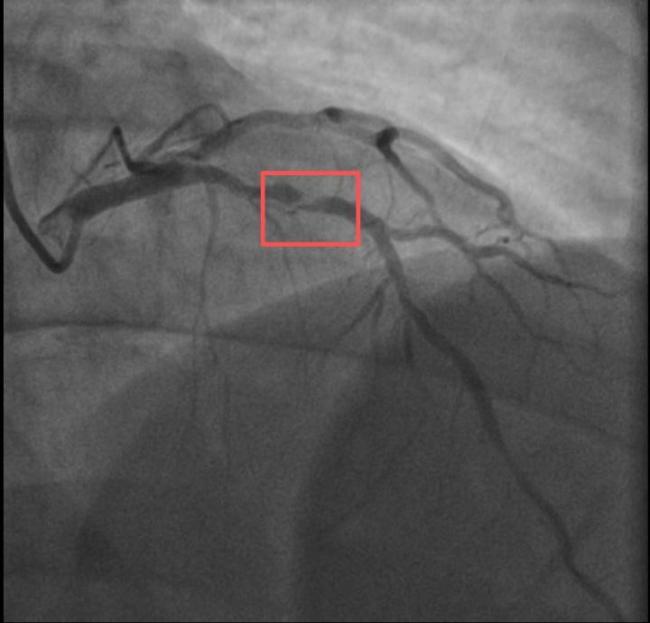

两个38岁的宝爸同一天因为急性心梗被送进医院,且都发生在剧烈运动后。一位陪孩子打了10分钟羽毛球,另一位陪孩子爬了一次山。这两位父亲的情况引发了人们的关注。孙先生是一位羽毛球教练,身高173cm,体重约90KG